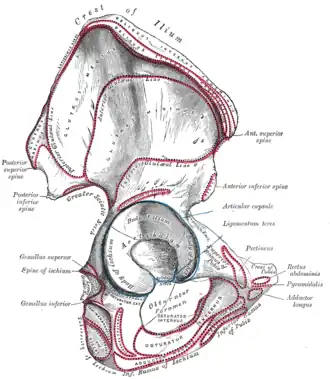

_-_Fig._349.png) Gluteus maximus of right side: outline and attachment-areas.

Gluteus maximus of right side: outline and attachment-areas. -

Image showing the outer surface of the ilium, showing the inferior gluteal line

Image showing the outer surface of the ilium, showing the inferior gluteal line -